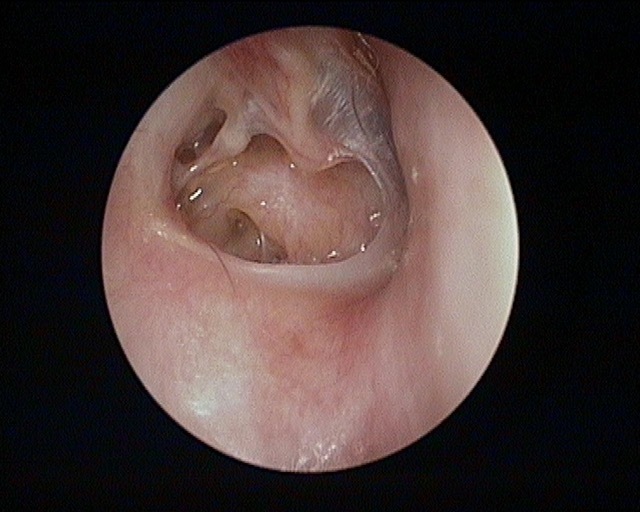

Perforation